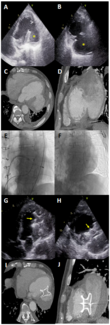

A 78-year-old male patient with a history of coronary artery disease, heart failure with mildly reduced ejection fraction, diabetes mellitus, and transient ischemic attack presented to the emergency department with complaints of dyspnea...